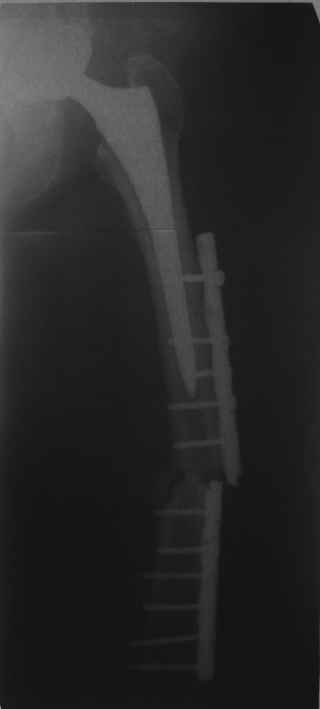

Уважаемые коллеги, в данном случае в лечении стандартного перипротезного перелома В2 Ванкуверской классификации (перелом вокруг ножки эндопртеза с потерей стабильности ножки при хорошем - не требующем пластики - качестве кости.Parvizi J, Rapuri VR, Purtill JJ, et al (2004) Treatment protocol for proximal femoral periprosthetic fractures. J Bone Joint Surg Am; 86-A Suppl 2:8-16)с успехом применён оригинальный, но малоизведанный способ лечения подобных повреждений. В результате и последующие рекомендации не могут быть стандартными. В подобных случаях, как это уже дискутировалось год назад, можно было выполнить ревизию длинной ножкой, во многом работающей как интрамедуллярный гводь + плюс кабель/серкляж в проксимальном отделе. Или, оставить имеющуюся ногу плюс длинная пластиа с кабелем/серкляжем, можно разными современными блокированными *примочками*. В таком случае при достижении консолидации пластина удаляется, тк при возникновении в будущем потребности в ревизии имеющийся дополнительный металл и без затруднит непростое вмешательство (кто пробовал, знает о чём я говорю). С длинной ногой, конечно, так же всё понятно. В данном случае мы имеем некую комбинацию, осложнённую отсутствием репозиции и фиксации в прошлом отломков вокруг ножки. Поэтому не каждый в данном случае рискнёт утверждать за счёт какого из компонентов системы - дистального либо проксимального обеспечивается стабильность. А если это и фиксация и за счёт ножки и за счёт гвоздя - каков баланс между данными компонентами в поддержании стабильности ситемы. То есть, я надеюсь, что дистального смещения ножки здесь не будет при условии сохранения как гвоздя, так и блокирующих винтов. При удалении же гвоздя возможна миграция ножки, только винтов - всей системы. Здесь же перелом (надеюсь, его не будет) блокирующих винтов может быть первым свидетельством механического неблагополучия системы... А так, помимо отличного результата этот случай так же косвенно подтверждает известную истину - Эндопротез, к сожалению, требует периодической замены. И выполняя фиксацию перипротезного перелома, а в последующем решая вопрос об удалении имплантатов, мы вынуждены думать и о функции сустава, и о том, как в будущем выполнить ревизию. Если ожидаемая продолжительность жизни пациента заставляет нас об этом думать. С уважением, Андрей

Это сплошной титановый стержень. На дистальном конце отверстия под кондуктор. На другом - канал под ножку глубиной 60 мм, стенки толщиной 2,5-3 мм. И там же продольный пропил, чтобы канал мог адаптироваться к ножке.